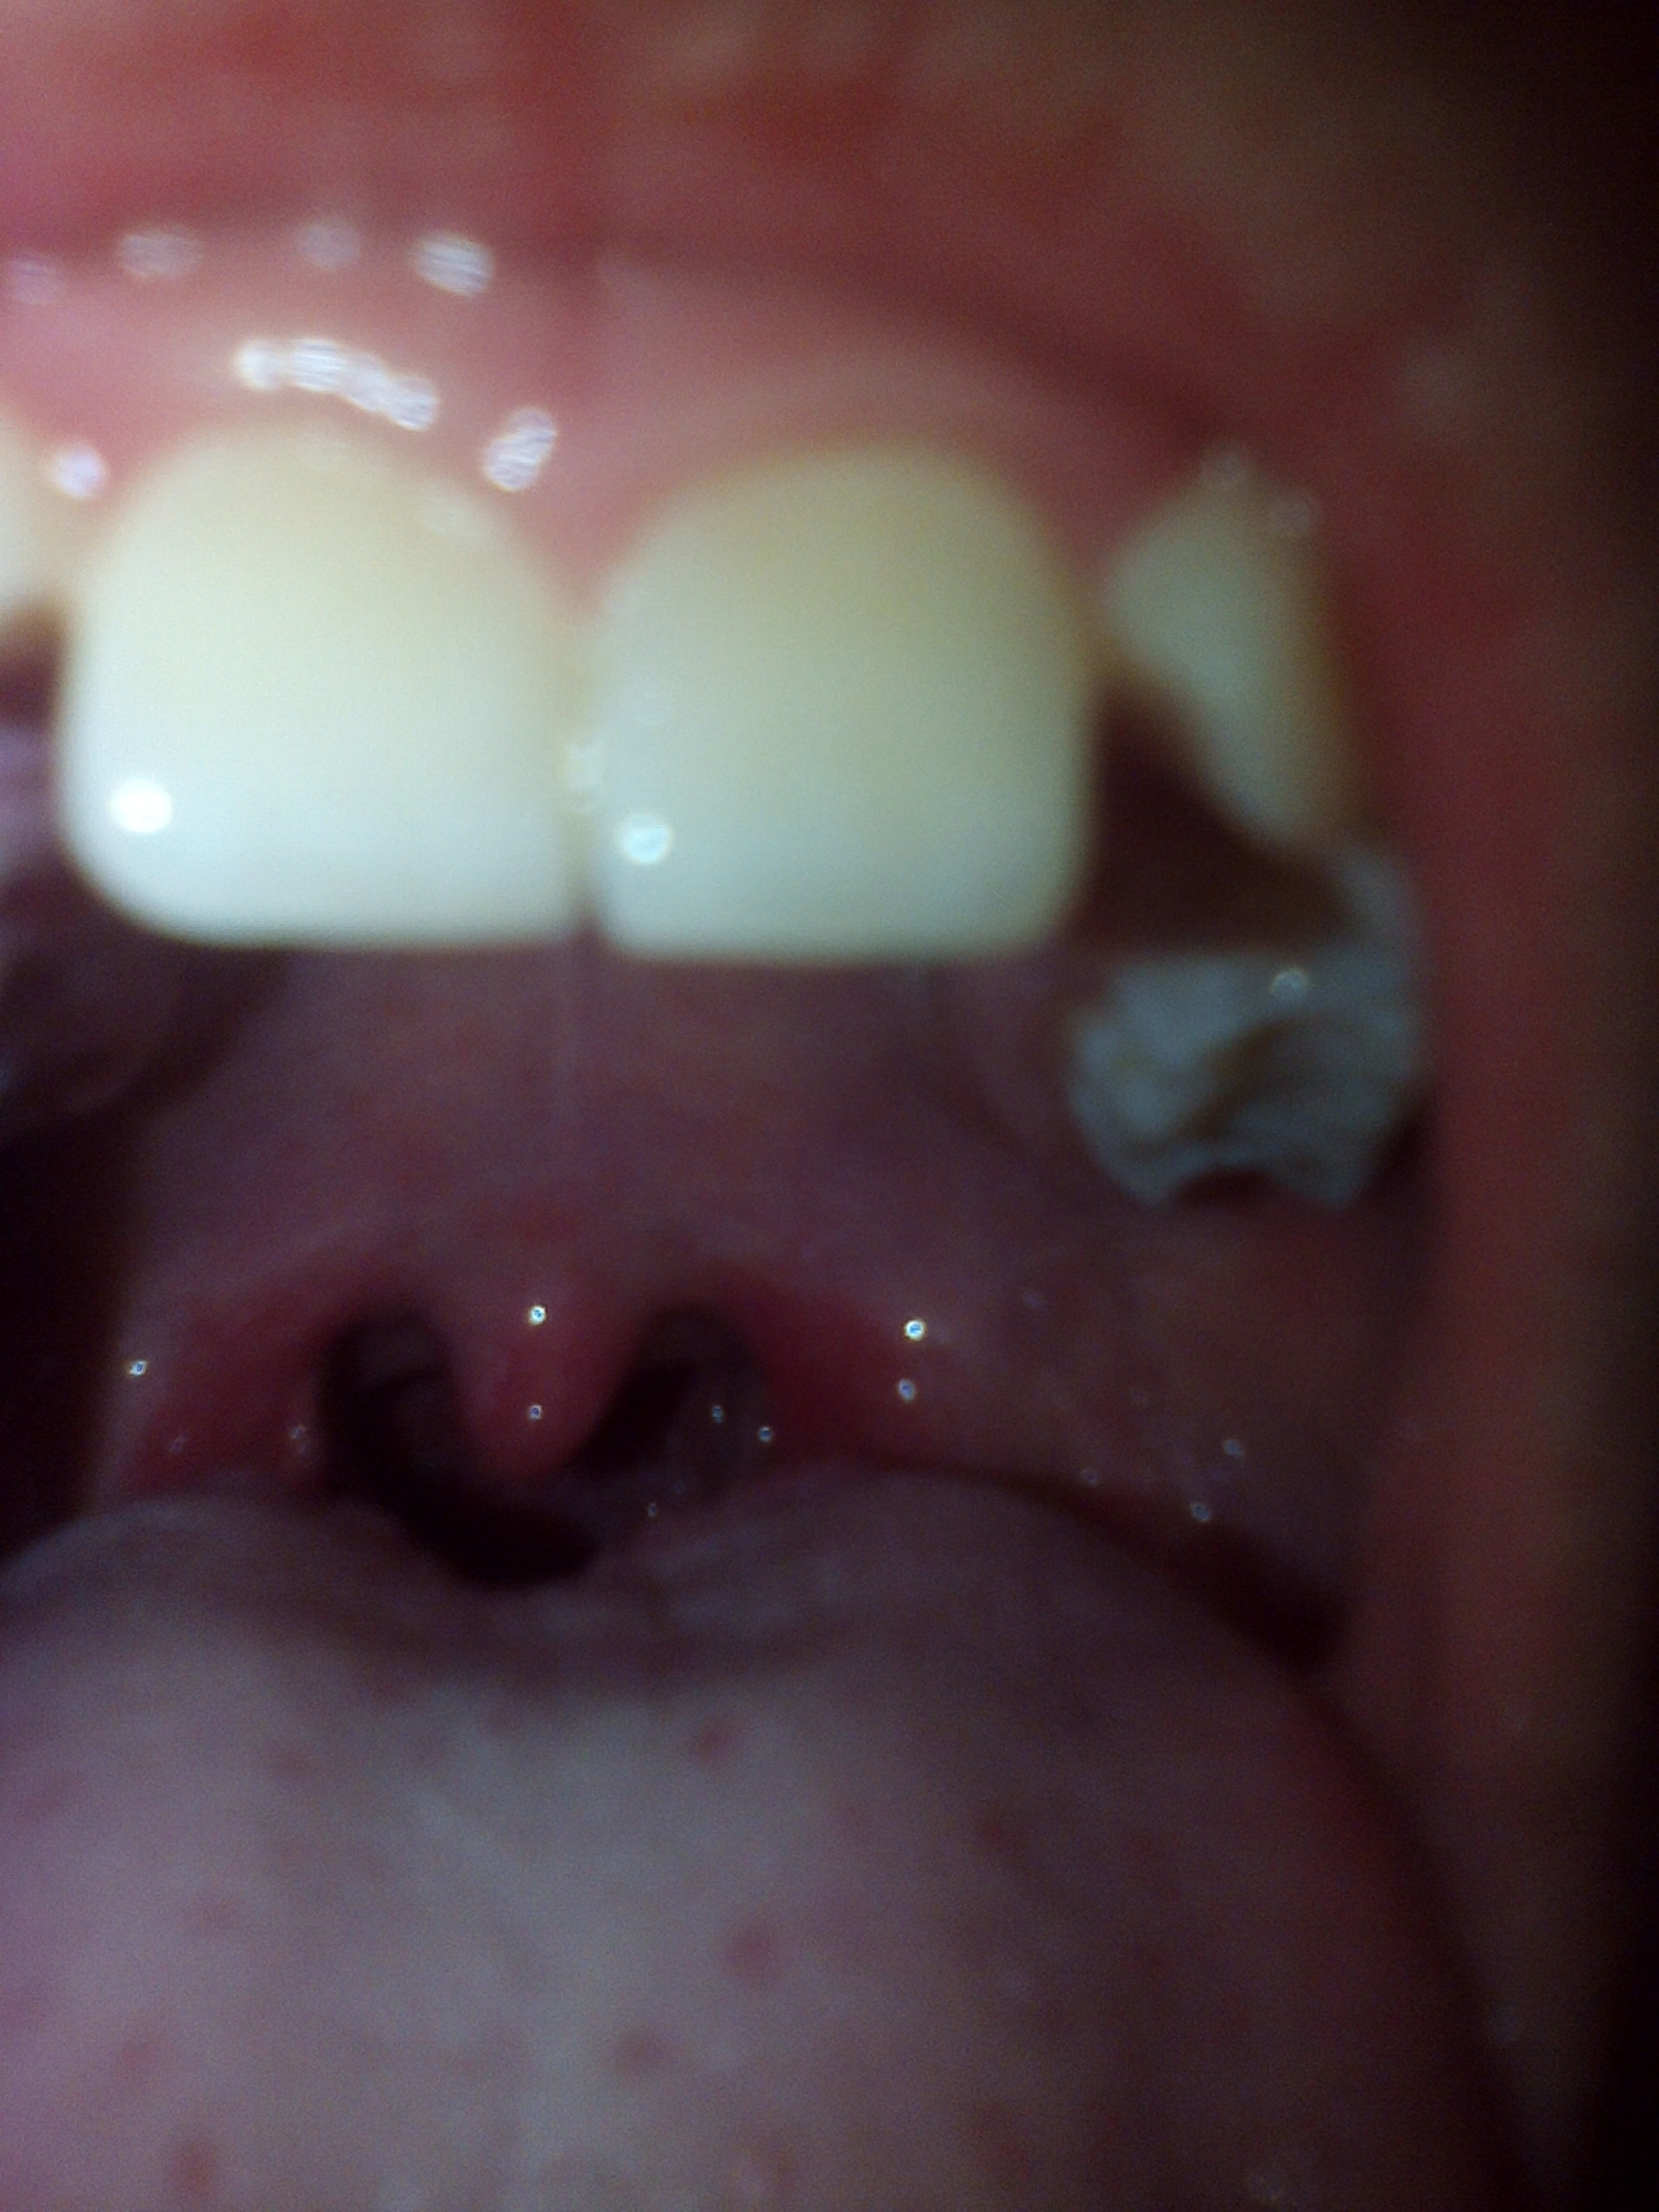

это горло здорового или больного человека.?

Больного оно всё красное

Качество фотографии не очень . Но при этом видно , что горло немного покраснело . Вывод ты простудился.